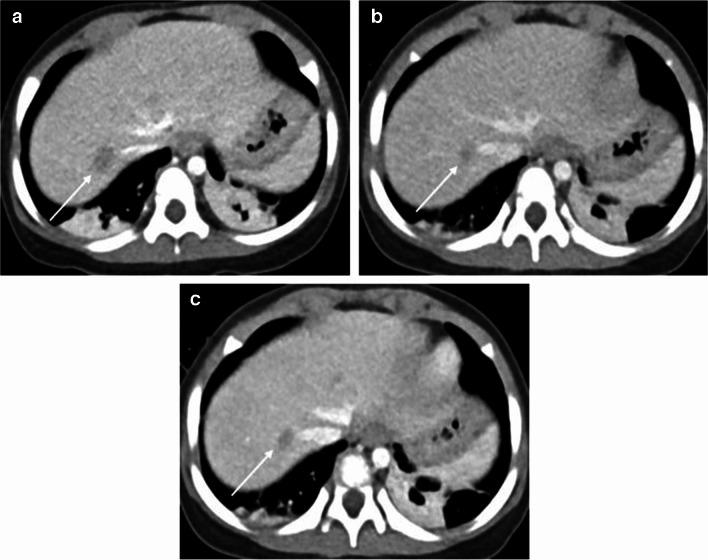

The standard-dose group exhibited higher attenuation, contrast-to-noise ratio (CNR), and signal-to-noise ratio (SNR) of organs and vessels compared to the low-dose group (all P-values < 0.05 except for liver SNR, P = 0.12). However, noise levels did not differ between the standard- and low-dose groups (P = 0.86). The contrast-boosted group had increased attenuation, CNR, and SNR of organs and vessels, and reduced noise compared with the low-dose group (all P < 0.05). The contrast-boosted group showed no differences in attenuation, CNR, and SNR of organs and vessels (all P > 0.05), and lower noise (P = 0.002), than the standard-dose group. In qualitative analysis, the contrast-boosted group did not differ regarding vessel enhancement and lesion conspicuity (P > 0.05) but had lower noise (P < 0.05) and higher organ enhancement and artifacts (all P < 0.05) than the standard-dose group. While iodine uptake was significantly reduced in low-iodine-dose CT (P < 0.001), there was no difference in radiation dose between standard- and low-iodine-dose CT (all P > 0.05).

Low-iodine-dose abdominal CT, combined with an AI-based contrast-boosting technique exhibited comparable organ and vessel enhancement, as well as lesion conspicuity compared to standard-iodine-dose CT in children. Moreover, image noise decreased in the contrast-boosted group, albeit with an increase in artifacts.

结果

与儿童标准碘剂量CT相比,低碘剂量腹部CT联合基于AI的造影剂增强技术在器官和血管强化以及病变清晰度方面表现相当。此外,造影剂增强组的图像噪声降低,尽管伪影有所增加。